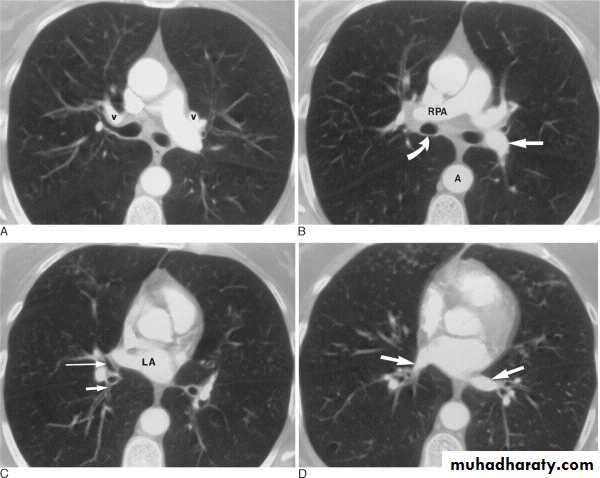

CT SCAN